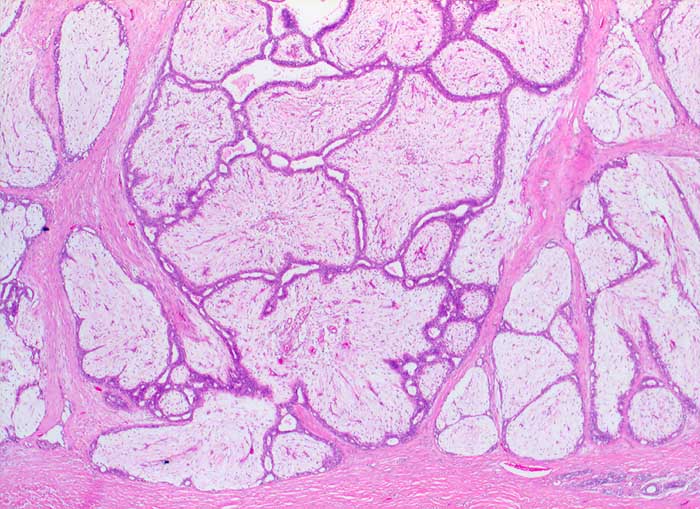

p/ Fibroadenom der Mamma

Fibroadenom der Mamma

Grosse Mengen epithelialer Zellen, bipolarer Nacktkerne (Myofibroblasten und Fibrozyten) und scharf begrenzte Stromafragmente charakterisieren das Fibroadenom zytologisch. Aspirate von stark fibrosierten Fibroadenomen können auch zellarm sein. Einseitig von Epithel bedeckte Bindegewebsfragmente sprechen für ein Fibroadenom. Durch die Aspiration wird die epitheliale Innenauskleidung mit ihren Verzweigungen aus dem Gangsystem gelöst. Die Epithelverbände sind beim intrakanalikulären Fibroadenom flach und erscheinen beim perikanalikulären Fibroadenom T-, Y-, finger- oder hirschgeweihförmig. Die Kerne sind wenig grösser als die Kerne normaler duktaler Epithelien und messen meist weniger als zwei Erythrozytendurchmesser. Da es sich bei Fibroadenomen um proliferierende Läsionen handelt können die Epithelzellen Zeichen der Aktivierung zeigen in Form einer mässig ausgeprägten Pleomorphie, prominenten Nukleolen, und gelegentlichen Mitosen.

Das erste Beispiel zeigt ein intrakanalikuläres, das zweite Beispiel ein perikanalikuläres Fibroadenom mit stark verzweigten Zellverbänden. Das dritte Beispiel zeigt die Zytomorphologie eines Fibroadenoms mit stark aktivierten Zellen.